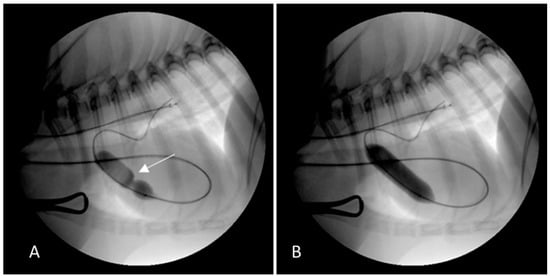

2.2. Case 2